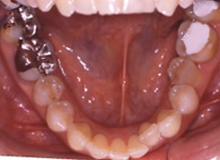

(治療前:写真左)

態癖の影響が強く奥歯が舌側に傾斜し、八重歯になっています。